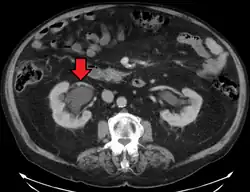

Massive hydronephrosis as marked by the arrow Massive hydronephrosis as marked by the arrow

Stone causing hydronephrosis[16]